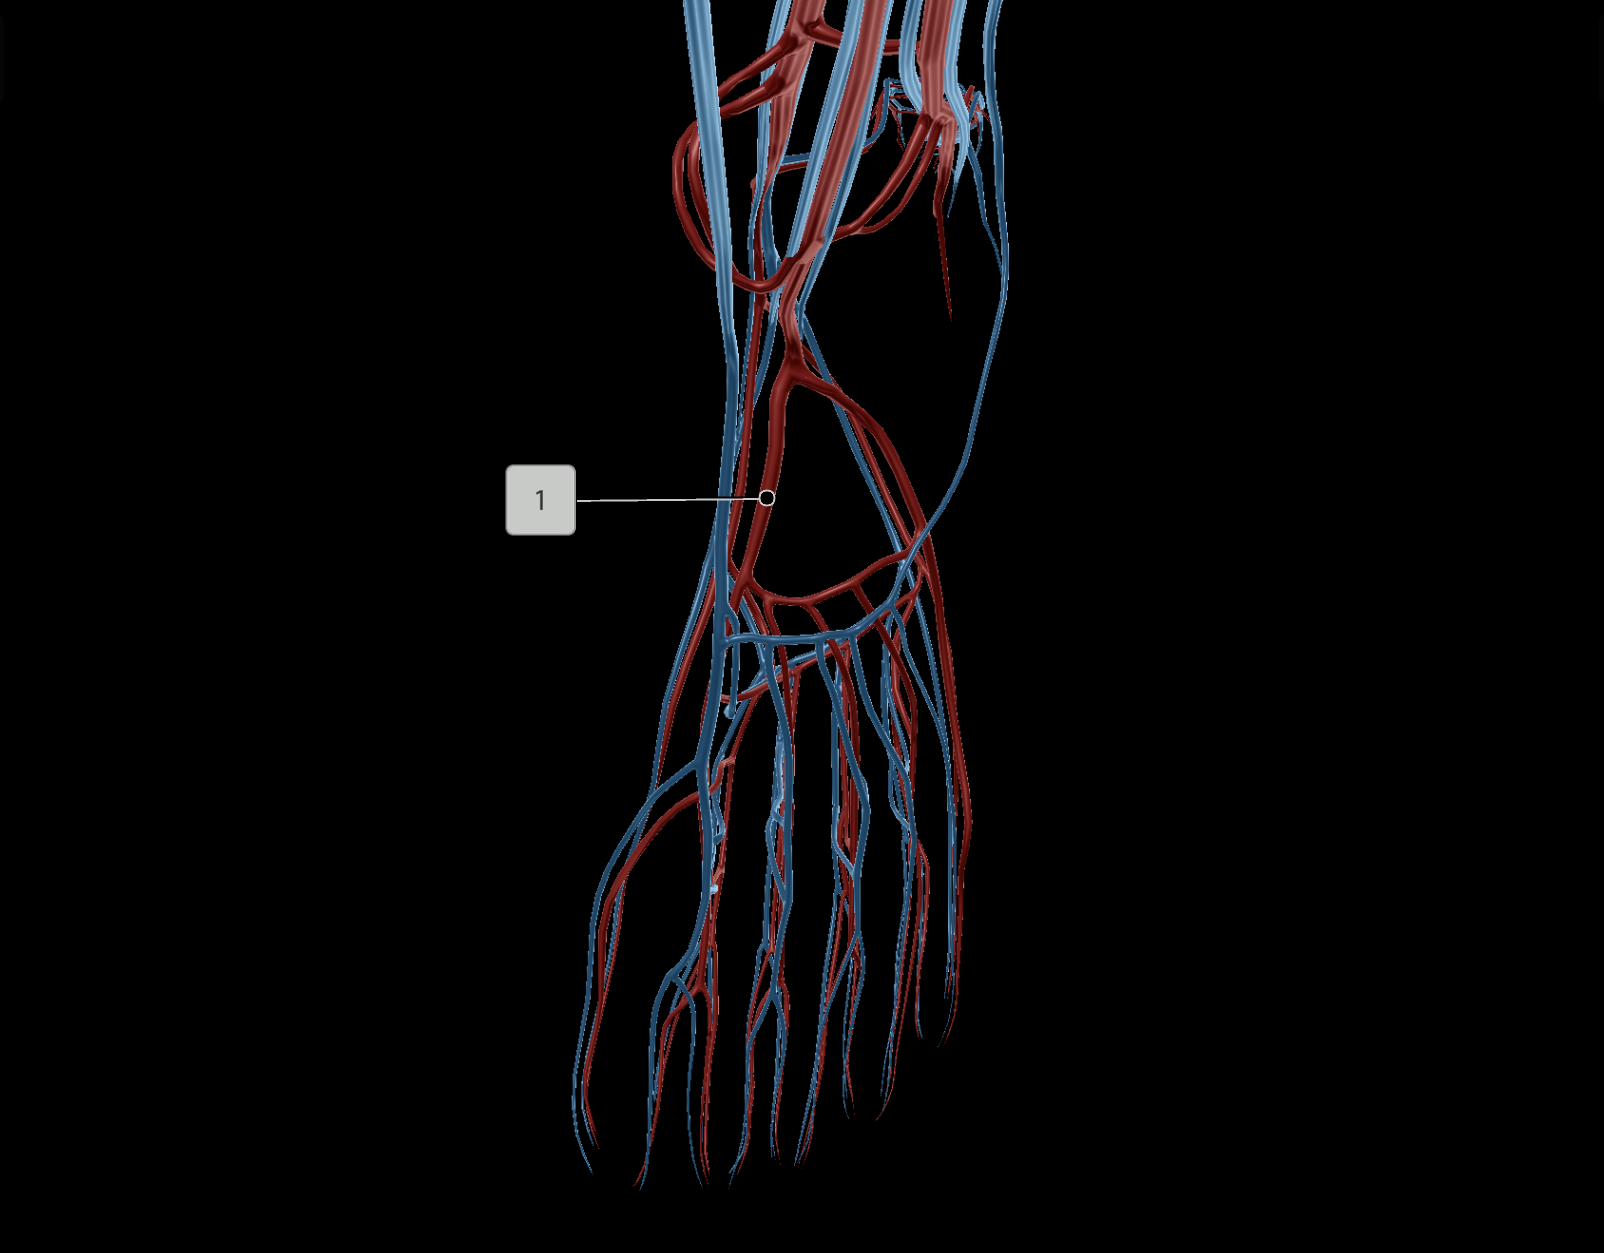

Anterior Tibial Artery

Posterior Tibial Artery

Dorsal Pedis Artery

Anterior Tibial Vein

Posterior Tibial Vein